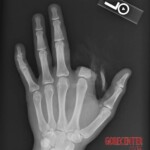

Boy stuck his hand into a terrarium with an alligator snapping turtle (Macrochelys temminckii). The turtle instinctively attacked and bit off and ate his entire finger. Doctors attempted to save the boy by removing the finger from the turtle’s stomach and sewing it back on. Whether this was successful is unknown.

As the name “alligator” suggests, this is not the slow-moving turtle you know from pet stores. The alligator snapping turtle is an extremely powerful predator with a jaw that can cause very serious injuries. Its reactions are almost instantaneous in order to catch fish. It can easily amputate the finger of an adult human.